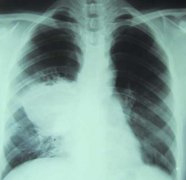

28岁小伙胸中藏长毛发的瘤 10多年常咳血(图)